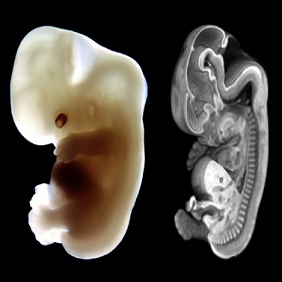

Human Embryo

Attaches to mother to feed.

The embryo attaches itself to the mother to feed, just like a leech attaches itself to a host to feed. The embryo also looks like a leech.

The embryo looks like a leech but these pictures are magnified by microscope; nobody knew this 1400 years ago. However this was portrayed in the Quran.

[Quran 23.14] Then We developed the semen into a leech. Then We developed the leech into a lump. Then We developed the lump into bones. Then We clothed the bones with flesh. Then We produced it into another creature. Most Blessed is Allah, the Best of Creators.

“Alaqa عَلَقَةً” means leech. It turned-out that the embryo looks like a leach. Then later it develops into a “Mudgha مُضْغَةً” meaning something chewed. It turned-out that at week 6 the vertebra of the embryo looks likes something chewed.